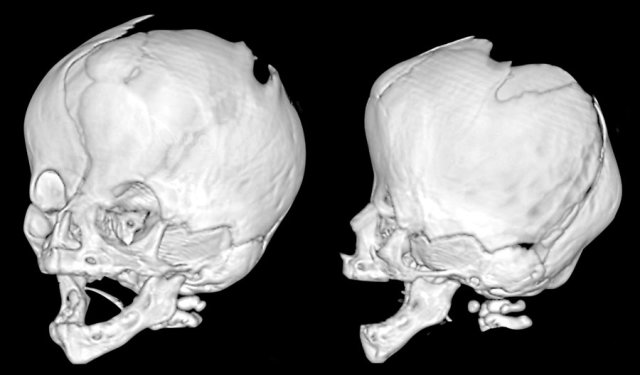

Images

Saethre-Chotzen syndrome. At two months of age there is a bilateral coronal synostosis with a severely deformed head shape. The fontanel is grossly enlarged.

Same patient as above.

At three years old there is microcephaly from a near pan-synostosis.

Note enlarged bilateral parietal foramina.

Three-month-old with Pfeiffer syndrome.

There is a bicoronal synostosis with enlarged anterior and mastoid fontanels.

Temporal bulging give rise to a trilobate appearance, also called ‘clover leaf deformity’.

Note the ventriculomegaly with periventricular edema.